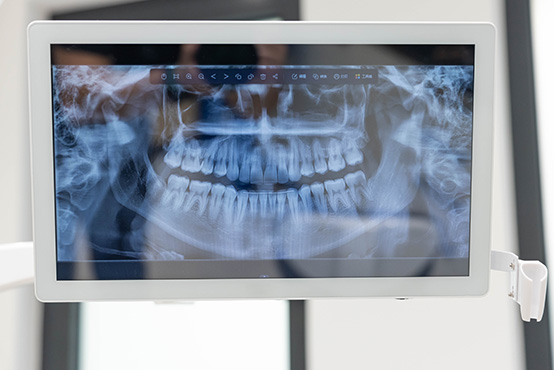

Dr. Linsky offers a comprehensive range of oral and facial surgical procedures, including dental implants, wisdom tooth removal, jaw surgery (orthognathic surgery), bone grafting, sinus lifts, TMJ treatment, and facial trauma care. Whether you’re seeking to restore missing teeth, correct jaw alignment, or relieve chronic pain, you can trust Dr. Linsky’s experience and precision. We combine advanced techniques with a personalized approach to help you achieve the healthiest, most functional, and most natural results possible.